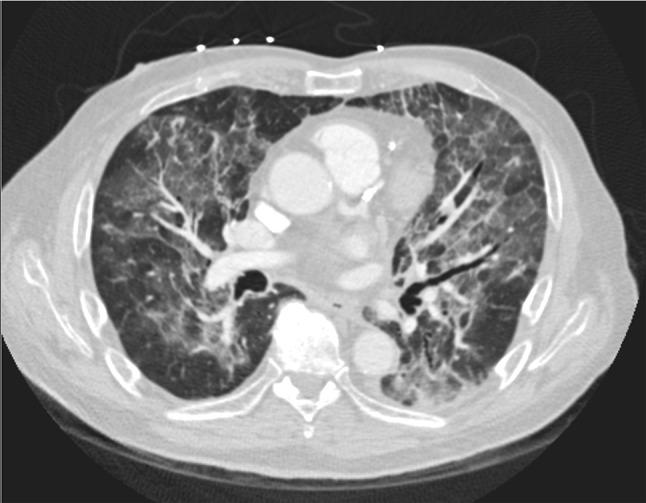

An 80-year-old male with recently diagnosed multiple myeloma undergoing treatment with lenalidomide and daratumumab presented with acute, rapidly progressive hypoxic respiratory failure ultimately requiring intubation and mechanical ventilatory support. Imaging revealed bilateral pulmonary opacities, however infectious workup was negative, and he was ultimately diagnosed with lenalidomide-induced interstitial pneumonitis, a rare but serious adverse effect of this medication. He was treated with drug discontinuation and methylprednisolone, and quickly recovered.

Lenalidomide is an immunomodulating medication used in the treatment of multiple myeloma, and is associated with rare but serious cases of drug-induced interstitial pneumonitis. Thus, if a patient receiving lenalidomide develops shortness of breath and/or hypoxia, drug-induced pneumonitis must be on the differential. Permanent drug discontinuation with or without corticosteroids is the mainstay of treatment, and patients are often able to fully recover, underscoring the need for early recognition of this condition.